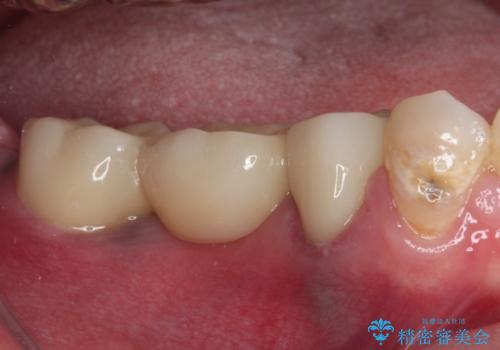

根管治療実施後は速やかに痛みが引き、仮歯で食事を取っても痛むことはなくなりました。

親知らずもむし歯が進行していたため、抜歯をし、傷の治りを待ってブリッジによる補綴治療を行いました。